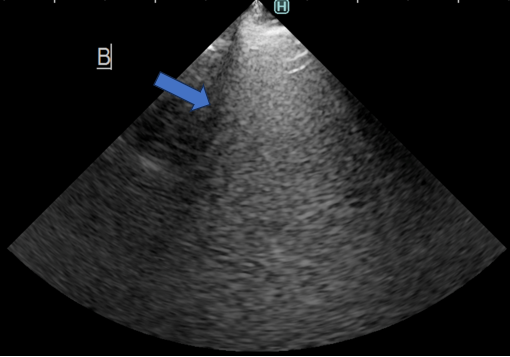

立位での胸部エコー検査にて肺水腫や肺炎などの病変を疑うBラインが認められました。